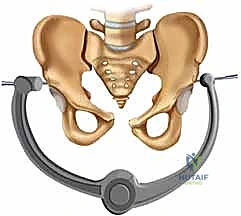

| طريقة العلاج | الراحة التامة في السرير لأسابيع، استخدام حزام الحوض (Pelvic Binder)، مسكنات الألم. | تدخل جراحي لرد العظام وتثبيتها ميكانيكياً باستخدام صفائح ومسامير معدنية. |

بعد تنظيف المفصل من أي أنسجة متمزقة أو جلطات دموية، يتم استخدام ملاقط عظمية خاصة (Pelvic Reduction Forceps) لجذب عظام العانة المنفصلة وإعادتها إلى موضعها التشريحي الصحيح بدقة مليمترية.

بمجرد استعادة الوضع الصحيح للعظام، يقوم الدكتور هطيف بتثبيتها باستخدام صفيحة معدنية متخصصة (غالباً صفيحة إعادة بناء متعددة الثقوب مصنوعة من التيتانيوم أو الفولاذ المقاوم للصدأ الطبي). يتم تثبيت هذه الصفيحة عبر المفصل العاني باستخدام مسامير قشرية (Cortical Screws) تُغرس بعمق في عظام العانة الصلبة لضمان تثبيت قوي يتحمل ضغط الجسم.